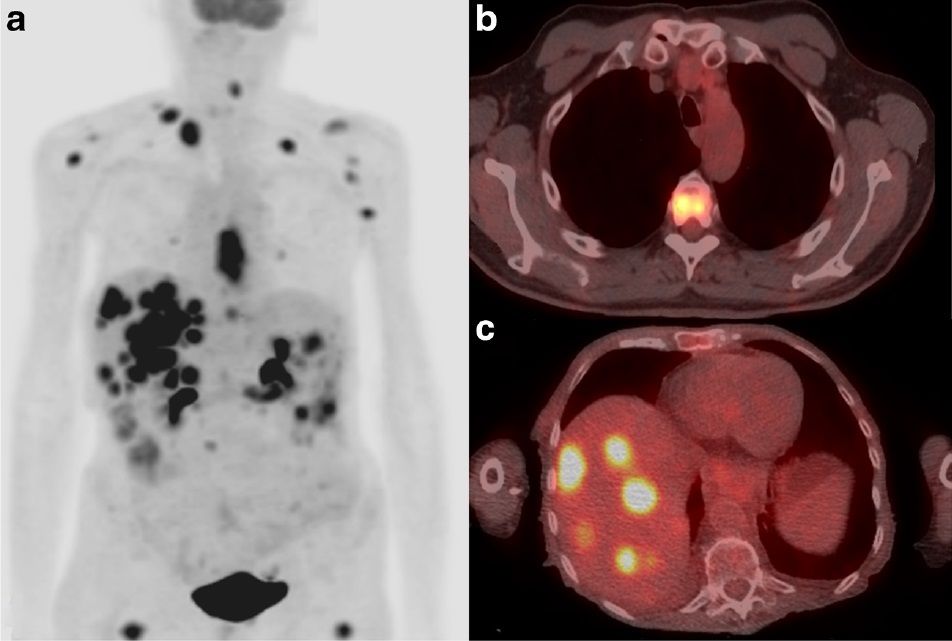

PET CT

Tomografia por emision de positrones para estudio de metastasis. GES garantiza en cancer de prostata, cintigrama oseo(metastasis) y escanner (compromiso ganglionar y ve mestastasis >1cm) PET CT: Sirve para ver compromiso ganglionar y metastasico en cancer de prostata PET PSMA: antigeno de superficie prostatico que se marca con Galio y marca la cleula prostatica tumoral.